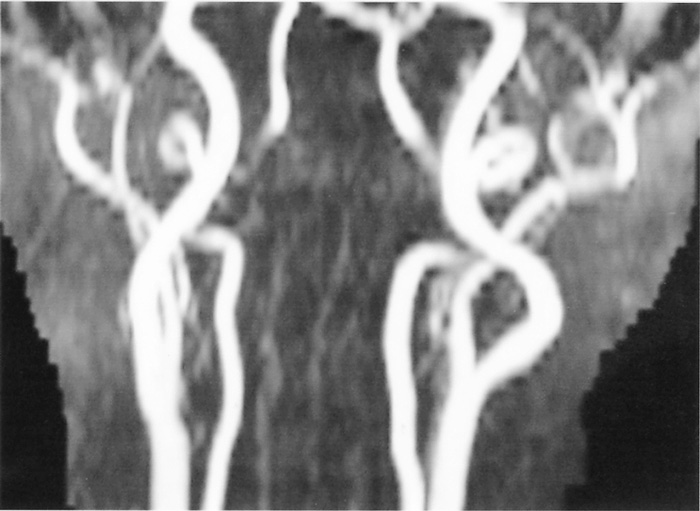

MR angiography demonstrating stenosis at the siphon of the right carotid artery.